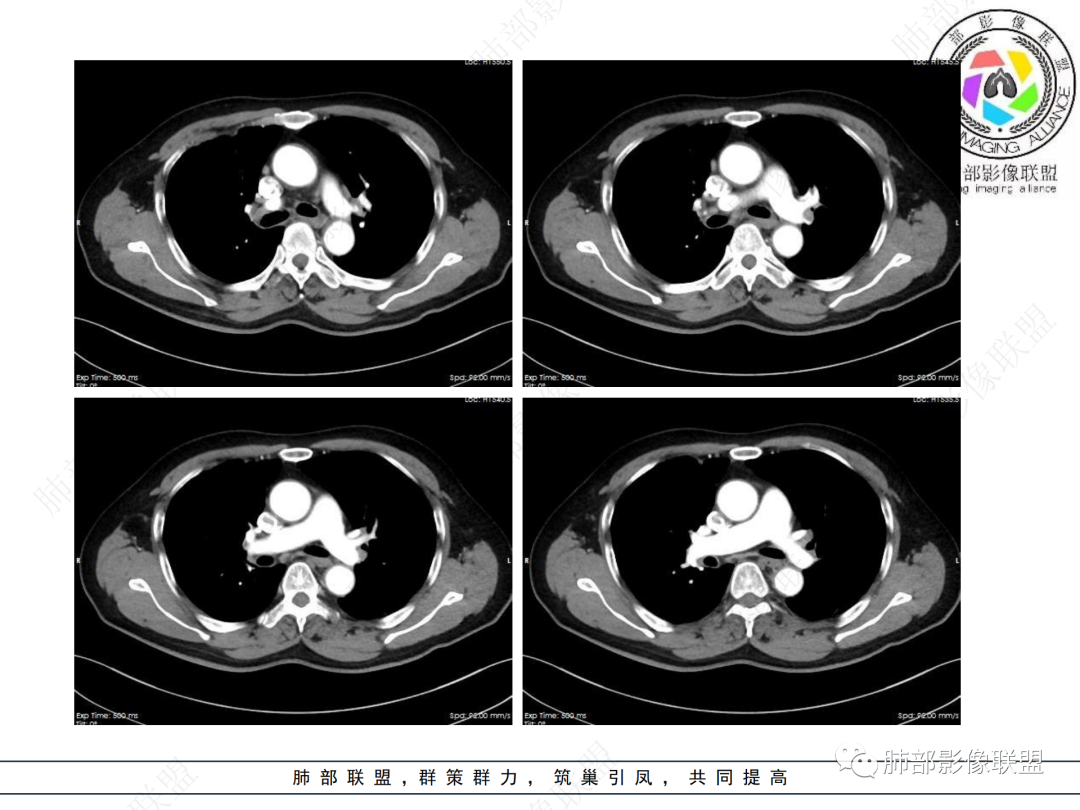

主要在慢性炎性病变与腺癌之间鉴别,病灶有膨胀性生长,支气管未见阻塞,支气管僵硬,增强病灶内可见强化,支气管内部壁增厚,偏向占位性病变,腺癌可能。

病史2年。右肺上叶团片影,边缘部分清晰,平直,相邻纵隔侧胸膜黏连较广泛,周围见斑点。增强均匀强化。首选炎性肉芽肿性病变(慢性炎症,结核)。肿瘤性病变待排。食道上段形态异常建议相关检查。

右上胸廓缩小,叶间裂移位,尖段软组织影,前段支气管壁增厚,双上肺多发结节及条片影,增强后尖段软组织影内见多发低密度影,呈环状强化,考虑慢性肉芽肿,腺癌待排

右肺上叶尖后段不规则斑块病灶,后缘以斜裂为界,有边缘平直,周围见纤维及多发小卫星灶,邻近胸膜反应性增厚,纵隔胸膜下少量积液,同时右肺中叶内侧段支气管扭曲及牵引性扩张,周边见爬行征,胸廊入口变窄,纵隔未见淋巴结肿大,综合上述慢性炎性肉芽肿,结核可能性大,支气管镜肺泡灌洗!